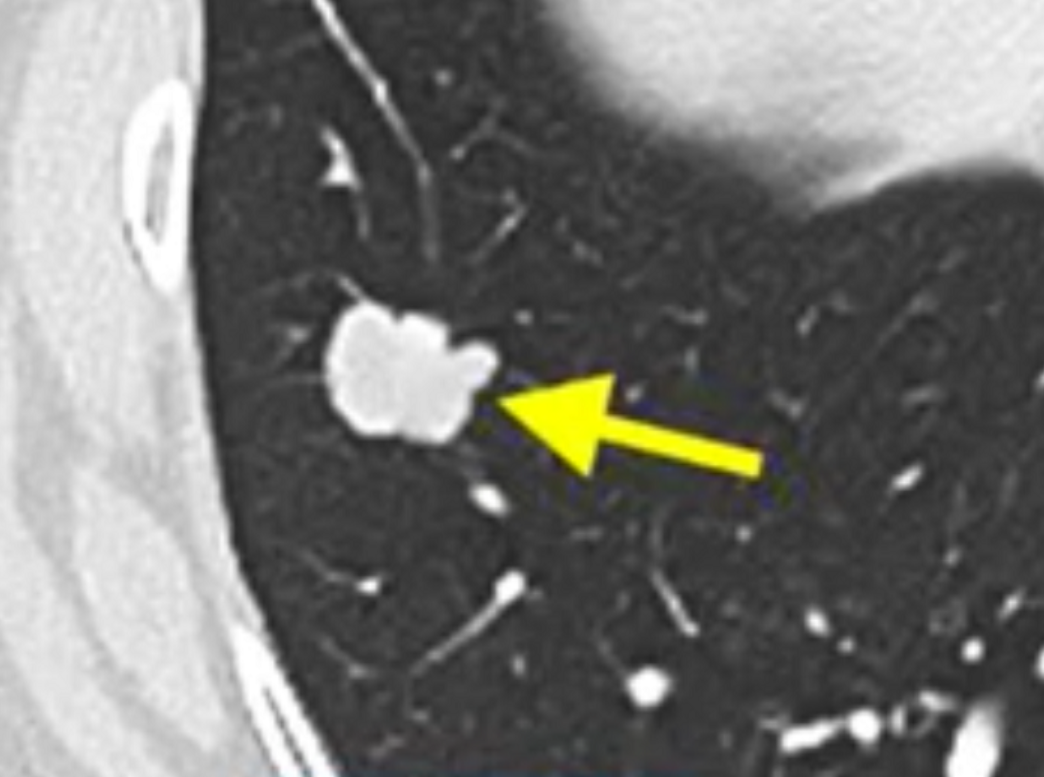

40天后,Ryan女士第一次复查惊讶的发现,肺上剩余的7个转移病灶已经全部消退,其中三个完全消失,医生们惊呼这是新型免疫疗法带来的又一例奇迹,Ryan女士在4年后仍然没有疾病进展,并且和Bachini女士成为好朋友。